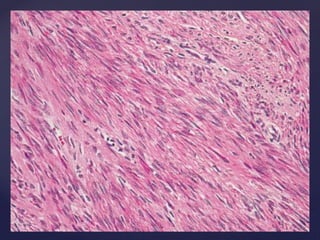

MORPHOLOGY

BODY/CORPOREAL FIBROIDS GROSSAPPEARANCE  CIRCUMSCRIBED DISCRETE ROUND FIRM,GRAY WHITE TUMORS SIZE VISIBLE NODULES TO MASSIVE TUMOR CUT SECTION  SMOOTH AND WHITISH  WHORLED APPEARANCE

• #15 . On cut surface the tumor has a glistening, pearl-white appearance, with the smooth muscle arranged in a trabeculated or whorled configuration. smooth muscle cells are markedly elongated and have eosinophilic cytoplasm and elongated, cigar-shaped nuclei.